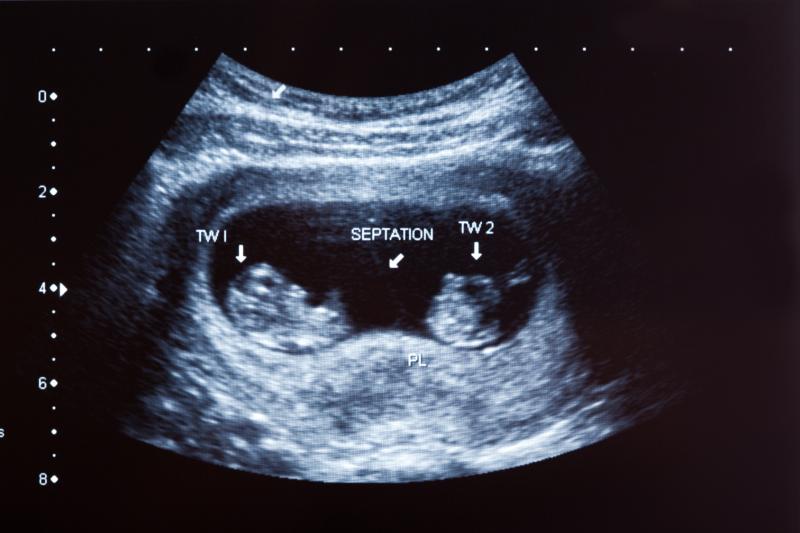

Antenatal betamethasone lowers risk of respiratory morbidity in late preterm twin neonates

Antenatal administration of betamethasone in women with twin pregnancies at risk of late preterm delivery appears to reduce the risk of neonatal respiratory morbidity, as shown in a study.